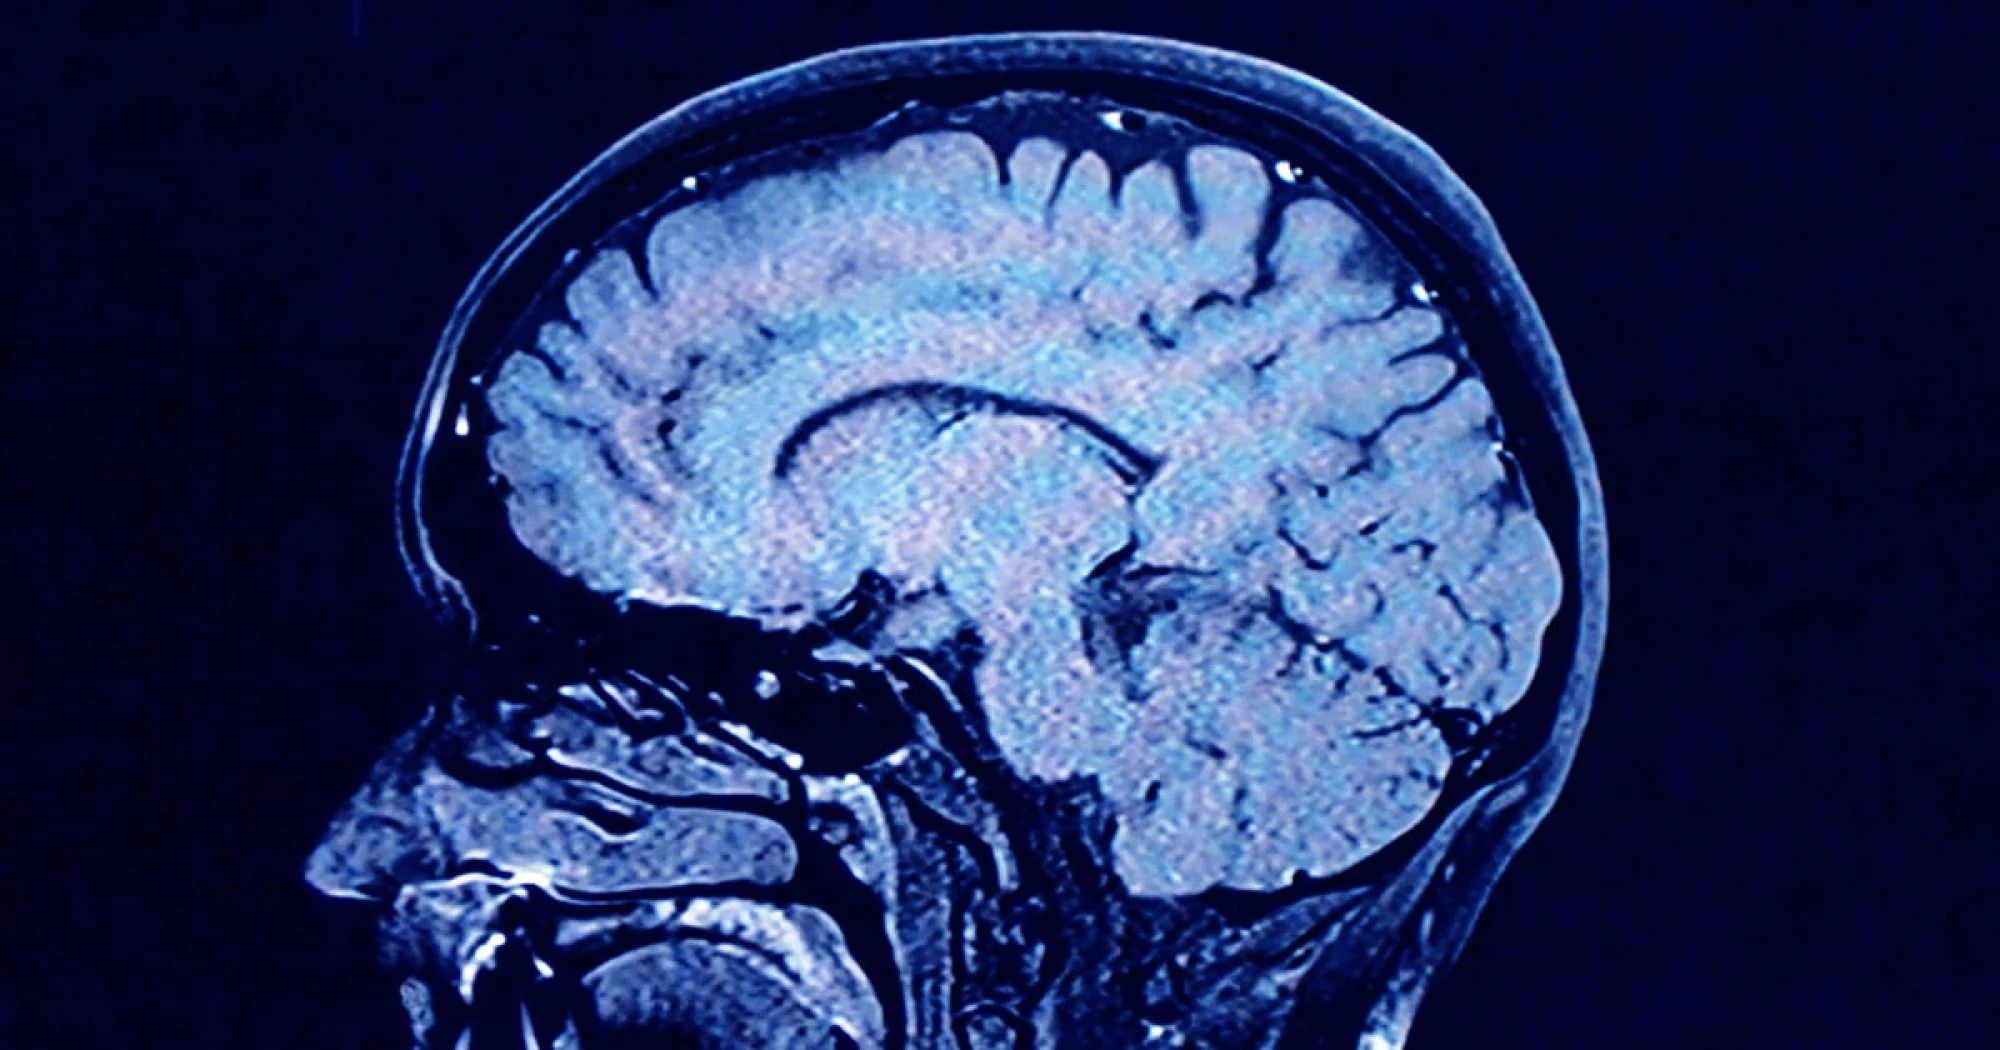

Human brains have 5 distinct 'epochs' in a lifetime, study finds

As we age, the human brain rewires itself.

The process happens in distinct phases, or “epochs,” according to new research, as the structure of our neural networks changes and our brains reconfigure how we think and process information.

For the first time, scientists say they’ve identified four distinct turning points between those phases in an average brain: at ages 9, 32, 66 and 83. During each epoch between those years, our brains show markedly different characteristics in brain architecture, they say.

The findings, published Tuesday in the journal Nature Communications, suggest that human cognition does not simply increase with age until a peak, then decline. In fact, the phase from ages 9 to 32 is the only time in life when our neural networks are becoming increasingly efficient, according to the research.

During the adulthood phase, from 32 to 66, the average person’s brain architecture essentially stabilizes without major changes, at a time when researchers think people are generally plateauing in intelligence and personality.